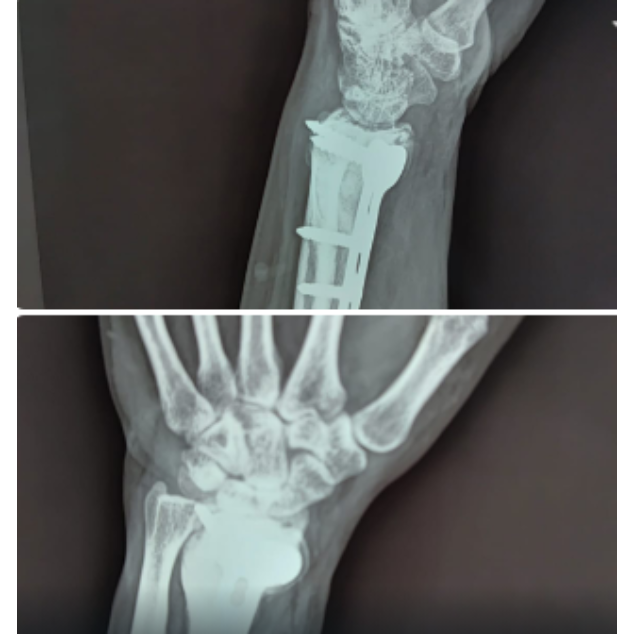

Giant cell tumour with pathological fracture 6 months post op x ray !